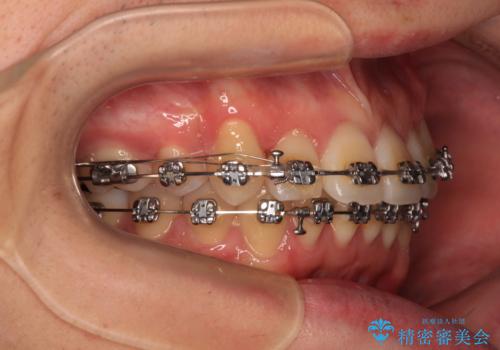

- 矯正装置

- メタルブラケット

- 治療期間

- 2年11ヶ月

- 治療回数

- 30回以上